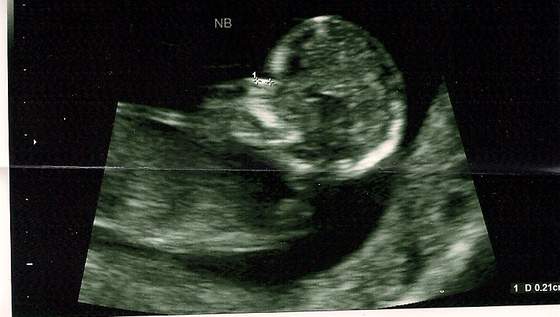

To ja tez sie pochwale swoim malym "Kosmita":-D. Dzis bylam na usg genetycznym 13 tc- CRL 6,77 wszystko jest w jak najlepszym porzadku, dzidzia zdrowa :-) tylko bardzo skakal i sie krecil i nie dalo sie okreslic jeszcze plci. Moj M. byl zachwycony :-) pierwszy raz byl ze mna na usg i bardzo duzo pytan zadawal :-). Wstawiam nizej zdjecia ale nie sa tak wyrazne jak bylo widac na moinitorze. Na pierwszym widac twarzyczke i pomiar kosci nosowej, to tu wyglada troche jak Kosmita :-D ale Pan doktor mowil ze to normalne:-), na drugim zdjeciu dzidzia w calosci widac nawet kregoslup. Pozdrawiam wszystkie dziewczeta i czekam na rownie dobre wiadomosci od innych :-)

Zobacz załącznik 440492Zobacz załącznik 440493